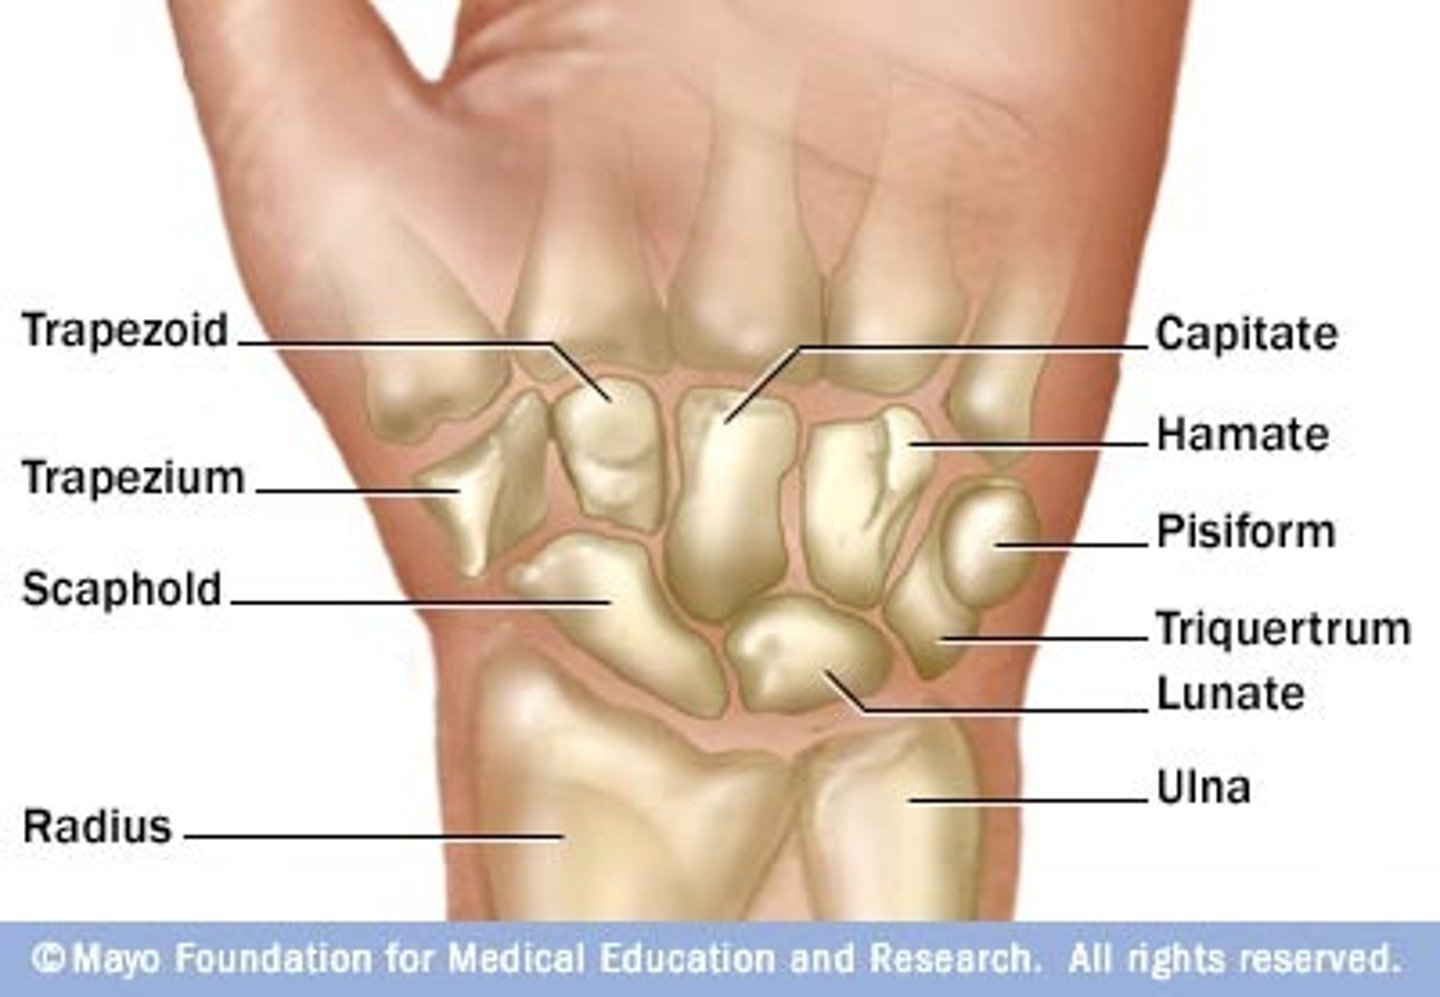

Characteristics of the wrist (or carpus):

- composed of 8 carpal bones arranged in proximal and distal rows of 4

- give flexibility to the wrest, each bone glide on the adjacent to it

- convex posteriorly and concave anteriorly (from side to side)

Proximal row of wrist bones (lateral to medial):

- scaphoid,

- lunate

- triquetrum

- pisiform

Scaphoid of the proximal row of the wrist:

- Largest bone in the proximal now

What does the scaphoid of the proximal row of the wrist articulate with?

Articulates with the radius

Lunate of the proximal row of the wrist:

Moon shaped